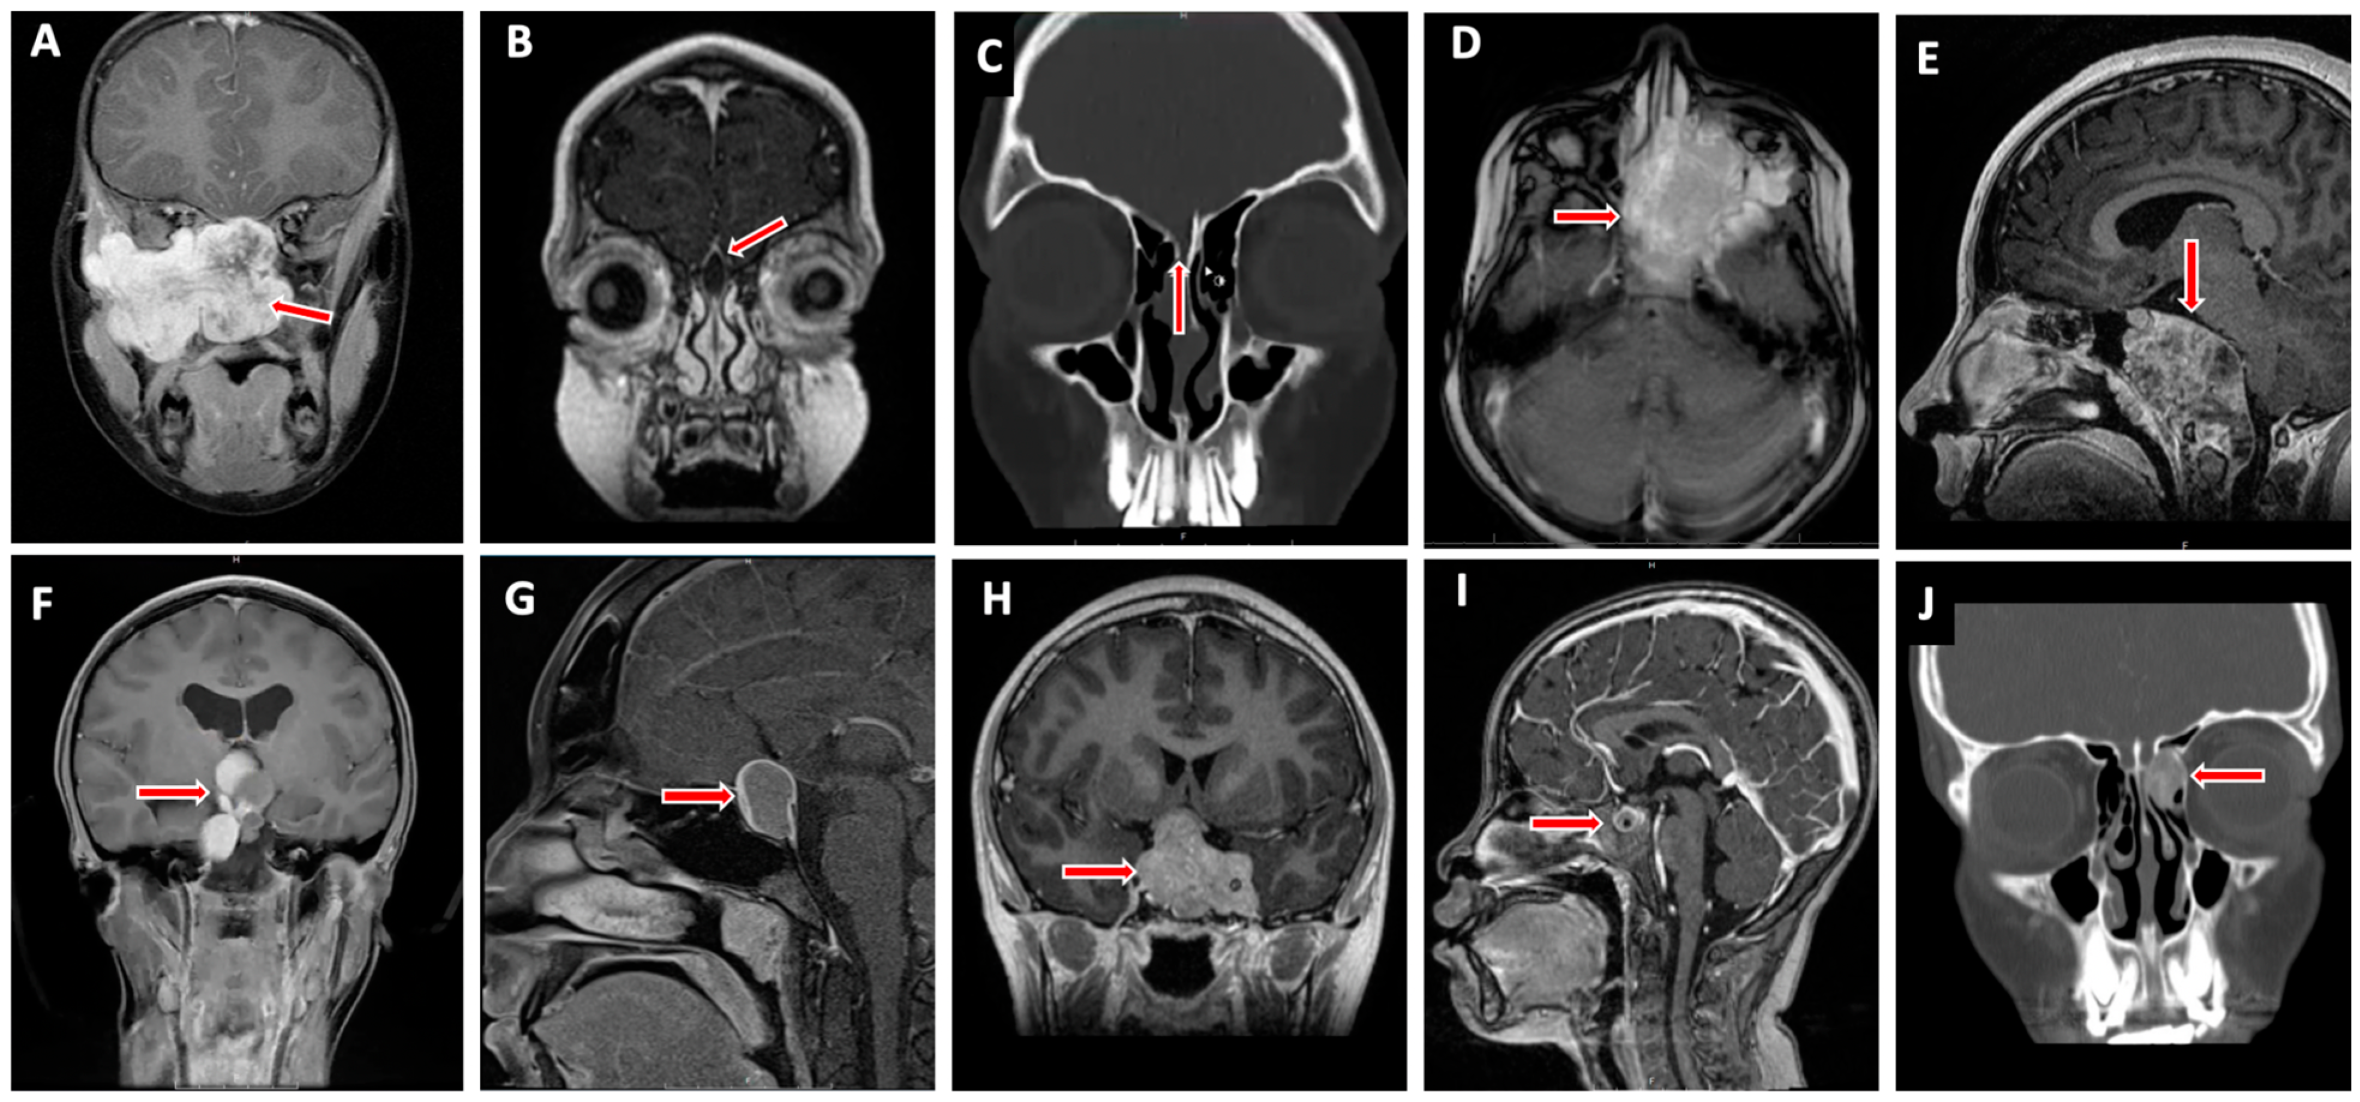

4. Pediatric Skull Base Pathology (Figure 2)

4.1. Anterior Cranial Fossa

4.1.1. Nasal Dermoid Cyst

4.1.2. Encephalocele

4.1.3. Juvenile Nasopharyngeal Angiofibroma

4.1.4. Esthesioneuroblastoma

4.1.5. Rhabdomyosarcoma

4.1.6. Fibrous Dysplasia

4.2. Middle Cranial Fossa

4.2.1. Rathke’s Cleft Cyst

4.2.2. Craniopharyngioma

4.2.3. Pituitary Adenoma

4.2.4. Germ Cell Tumor (GCT)

4.2.5. Langerhans Cell Histiocytosis/Eosinophilic Granuloma

4.3. Posterior Cranial Fossa

4.3.1. Chordoma/Benign Notochord Cell Tumor

4.3.2. Chondrosarcoma

4.3.3. Other Skull Base Lesions